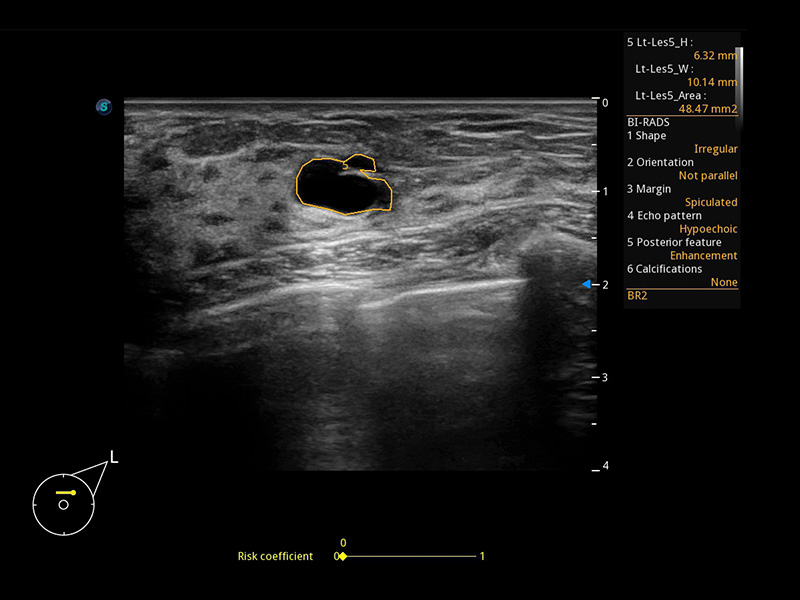

Micro F

Micro F bietet eine innovative Methode, um den sichtbaren Fluss in der Ultraschallbildgebung zu erweitern, insbesondere um den langsamen Fluss kleiner Gefäße sichtbar zu machen. Durch die Verwendung eines fortschrittlichen adaptiven Filters und die Akkumulation von zeitlichen und räumlichen Signalen kann Micro F den geringen Blutfluss effektiv von der Bewegung umgebendem Gewebe unterscheiden und die Hämodynamik mit höherer Empfindlichkeit und räumlicher Auflösung darstellen.

• Zervikales schlecht differenziertes Karzinom mit Micro F

• Fetale Pericallosal-Arterie mit Micro F

• Fetale einseitige Kleinhirnhypoplasie mit Micro F

• Fetaler Leberblutfluss mit Micro F